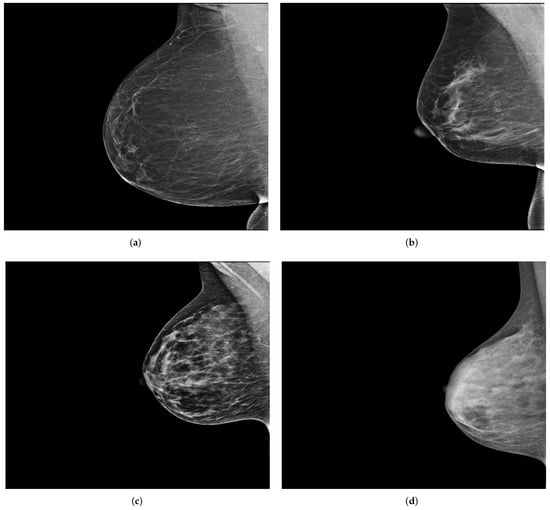

INbreast [15] is another public dataset that contains a total of 115 full-field digital mammography studies with CC and MLO views for each breast. These mammograms have different intensity profiles and higher image resolution compared to digitized film mammograms from the DDSM and MIAS datasets. Figure 1 shows a sample (MLO view of the right breast) from each of the previously mentioned publicly available datasets.

Each performed mammography exam includes four standard views: a CC and a MLO view for each, the right and left breast, as illustrated in Figure 3.

Figure 1. MLO views of the right breast from publicly available datasets. (a,b) A sample from the DDSM [13] and MIAS [14] dataset, respectively. (c) A sample from INbreast [15]. Reprinted/adapted with permissions from [13,14,15].

Figure 3. Example of a mammography study selected from the collected dataset showing the four standard views (ad). (a) right cranio-caudal (R-CC); (b) left cranio-caudal (L-CC); (c) right mediolateral oblique (R-MLO); (d) left mediolateral oblique (L-MLO).